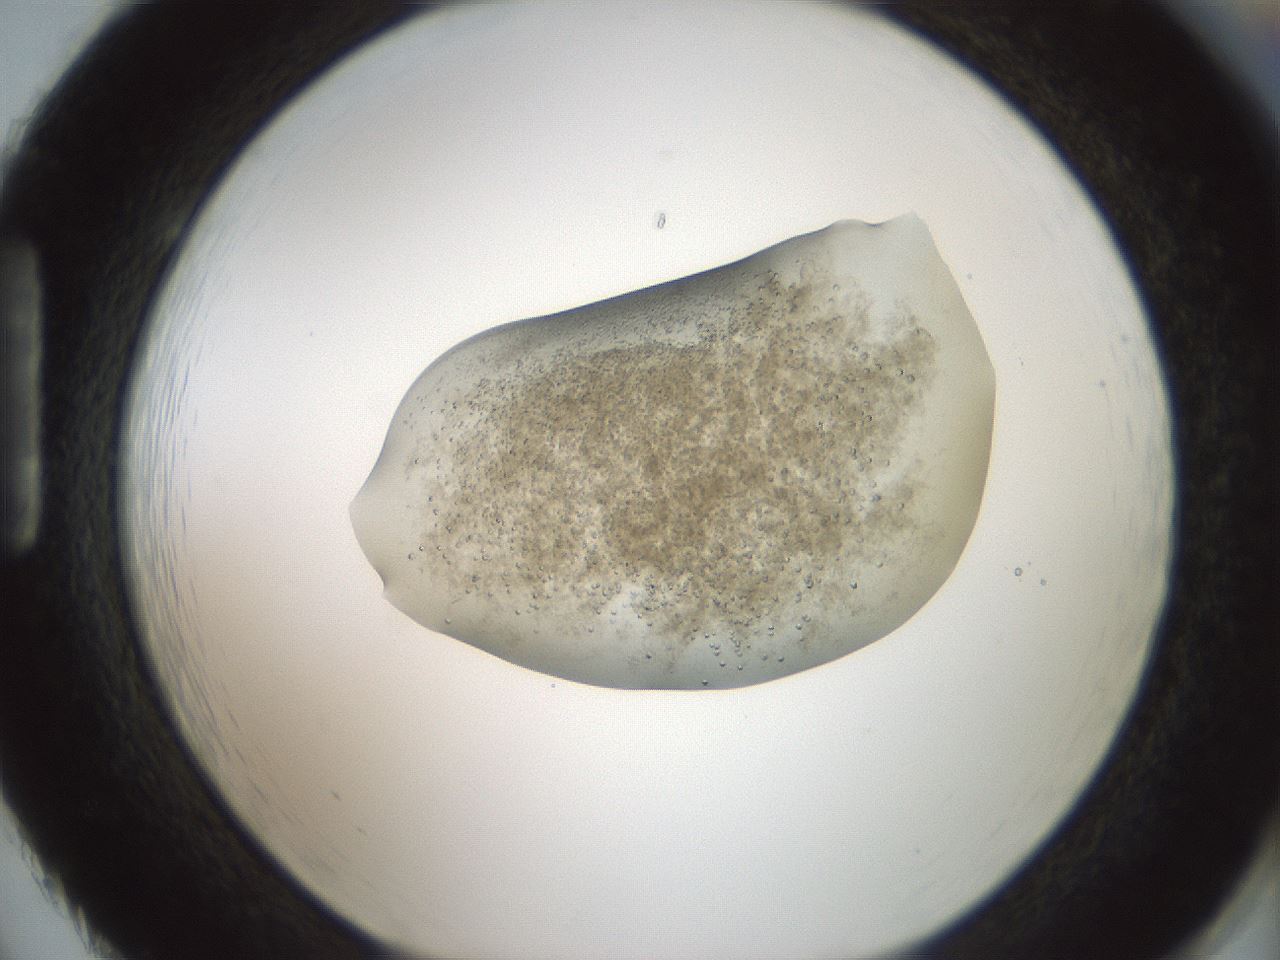

folderID100_plateID3100_batchID18819_wellNum86_profileID1_d1_r260734_ef.jpg